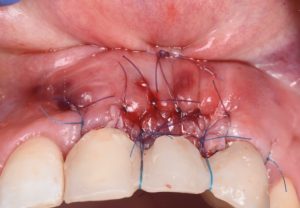

The procedure demonstrates the use of a horizontal vestibular incision with tunneling to mobilize the soft tissues and elevate the papillae. An autogenous connective tissue graft (CTG) harvested from the palate and maxillary tuberosity is utilized to augment tissue thickness. Additionally, a xenogenic bone graft is placed over the crestal area to serve as a space-maintaining scaffold and support vertical tissue stability.

Advanced flap advancement and suturing techniques are highlighted to ensure graft stability and optimal soft tissue outcomes.

- Advanced suturing strategies for flap advancement and stabilization